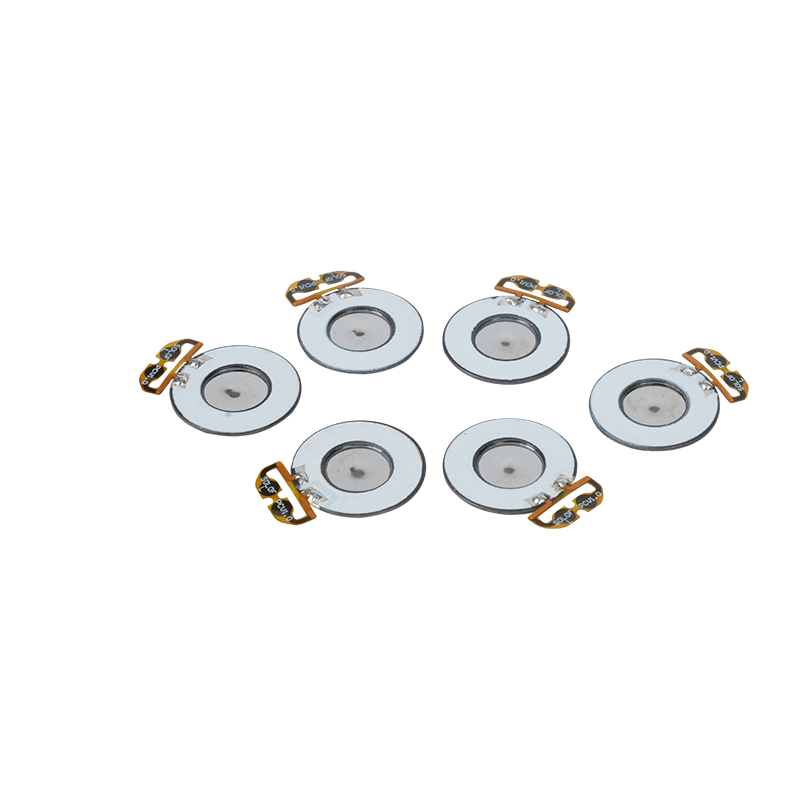

Lékařské síťové nebulizační tablety jsou přesné součásti používané v lékařských zařízeních k přeměně léků nebo roztoků na malé aerosolové částice pro léčbu různých respiračních poruch, jako je astma a chronická obstrukční plicní nemoc (CHOPN) atd. inhalací. Konstrukce a výběr materiálu vrstvy nebulizátoru je rozhodující pro zajištění účinného podávání léčiva a pohodlí pacienta. Nerezový membránový plech je v ocelovém plechu proražen tisíci malých 2-3μm síťových otvorů v ocelovém plechu pomocí technologie laserového vrtání v přesném laserovém procesu a poté je pevně spojen s piezoelektrickým keramickým kruhovým plechem, který převádí rezonanční frekvenci piezoelektrického plechu na vysokofrekvenční vibrační energii prostřednictvím výstupního signálu desky ovladače PCB a rychle rozbíjí kapalinu. léky na jemné aerosolové částice. Tyto kapičky se také nazývají střední velikost částic, když střední procento velikosti částic D50 dosáhne > 60 % nebo více, částice budou dostatečně malé, aby se mohly dýcháním dostat hluboko do plic k povrchu alveol, čímž se zlepší absorpční účinnost léku a terapeutický účinek. Micro mesh nebulizérový list Medical Mesh má hlavně několik forem, nerezový mikrosíťový nebulizační list, nikl-palladium lékařský nebulizační list, PI polymerový lékařský nebulizační list a tak dále. Všechny výše uvedené jsou prostřednictvím piezoelektrické keramické vibrační přeměny energie k dosažení atomizačního efektu.

Polyimid (Polyimid) označovaný jako PI, je nejlepší komplexní výkon organických polymerních materiálů, má vynikající chemickou stabilitu a může odolat korozi různých léků, aby bylo zajištěno dlouhodobé používání atomizovaných tablet. Kromě toho je vynikající tepelná stabilita polymerního PI filmu, s dlouhodobým používáním teplotního rozsahu -200 ~ 300 ° C, vysokou izolací, ochranou životního prostředí a netoxicitou, jako speciální inženýrský materiál, široce používaný v letecké mikroelektronice, separační membrány z nano-kapalných krystalů a další obory, byl v 21. století zahrnut zeměmi jednoho z nejslibnějších inženýrských materiálů. deformované v procesu vysokoteplotní dezinfekce, aby bylo zajištěno opětovné použití! Pro sex a bezpečnost používáme laserovou technologii pro laserovou perforaci, PI film implantovaný mezi nerezovou ocel a piezoelektrickou fólii, použití piezoelektrické keramické ultrazvukové technologie tak, aby se atomizované kapičky přes PI film rozptýlily do atomizace 3 ~ 4 μm částic pro inhalaci lékařskou nebulizací, bezpečnost většiny uživatelů miluje, vyrobeno z hlavního nebulizéru s PI výhoda non-ucpání, vnitřní stěna otvoru v hladké a zaoblené, žádné zbytky kapaliny, atomizace jemné a stabilní. Atomizace je jemná a stabilní. Tablety PI filmového nebulizátoru mohou účinně zabránit zbytkům léků, snížit riziko křížové kontaminace. V praktické aplikaci se také promítly charakteristiky nízké spotřeby energie polymerních PI membránových nebulizačních tablet, shrnuto, polymerové PI membránové nebulizační tablety se se svým vynikajícím výkonem a konstrukčními výhodami staly nepostradatelnou součástí oblasti lékařské nebulizační terapie.